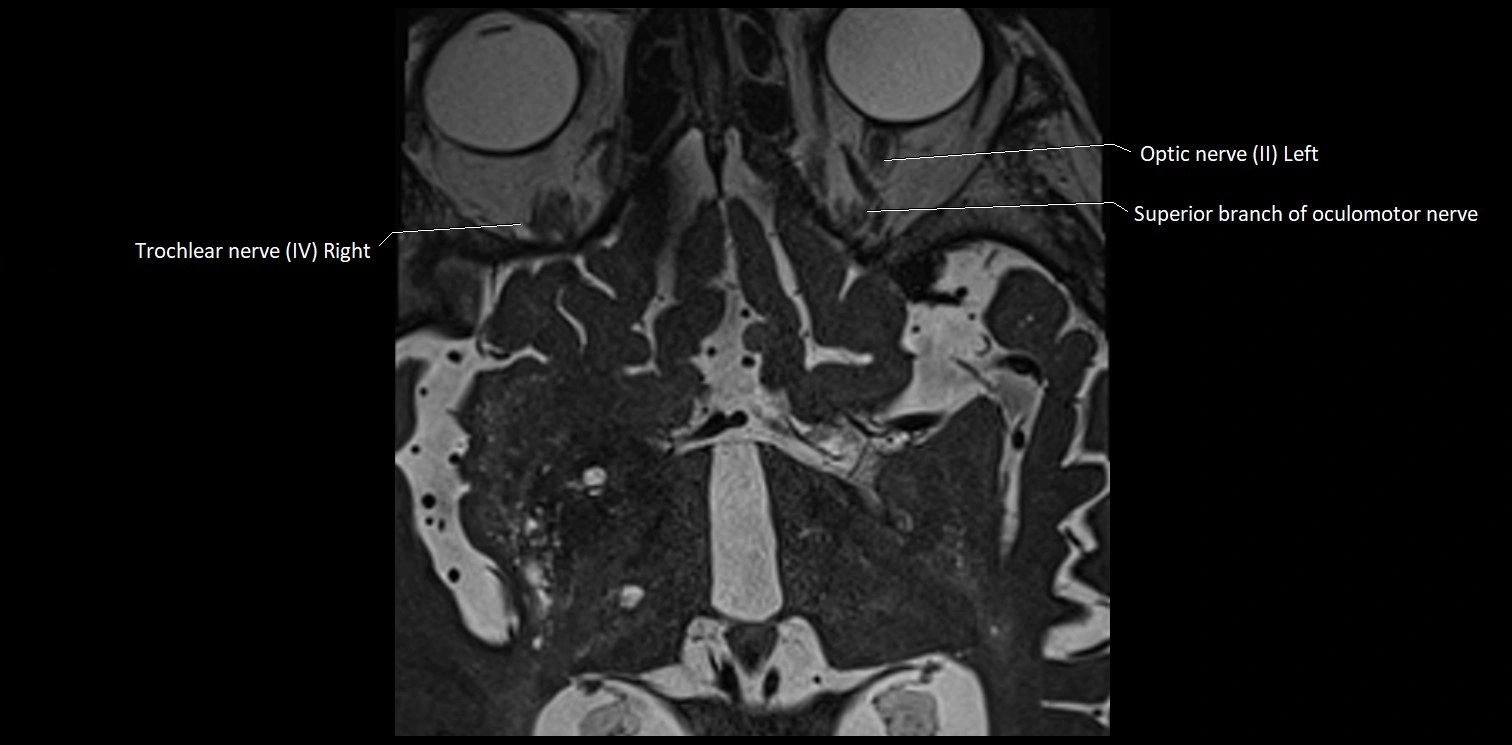

MRI Appearance

• The abducens nerve is a small, thin, linear structure

• Best visualized on high-resolution T2-weighted 3D MRI sequences (e.g., FIESTA or CISS)

• Seen as a hypointense (dark) line running from the brainstem at the pontomedullary junction, traversing the prepontine cistern, and entering Dorello’s canal under the petrosphenoidal ligament, then into the cavernous sinus, and finally the orbit

• May be challenging to visualize in standard MRI due to its small size

• Pathology may be inferred by absence, displacement, or enhancement of the nerve